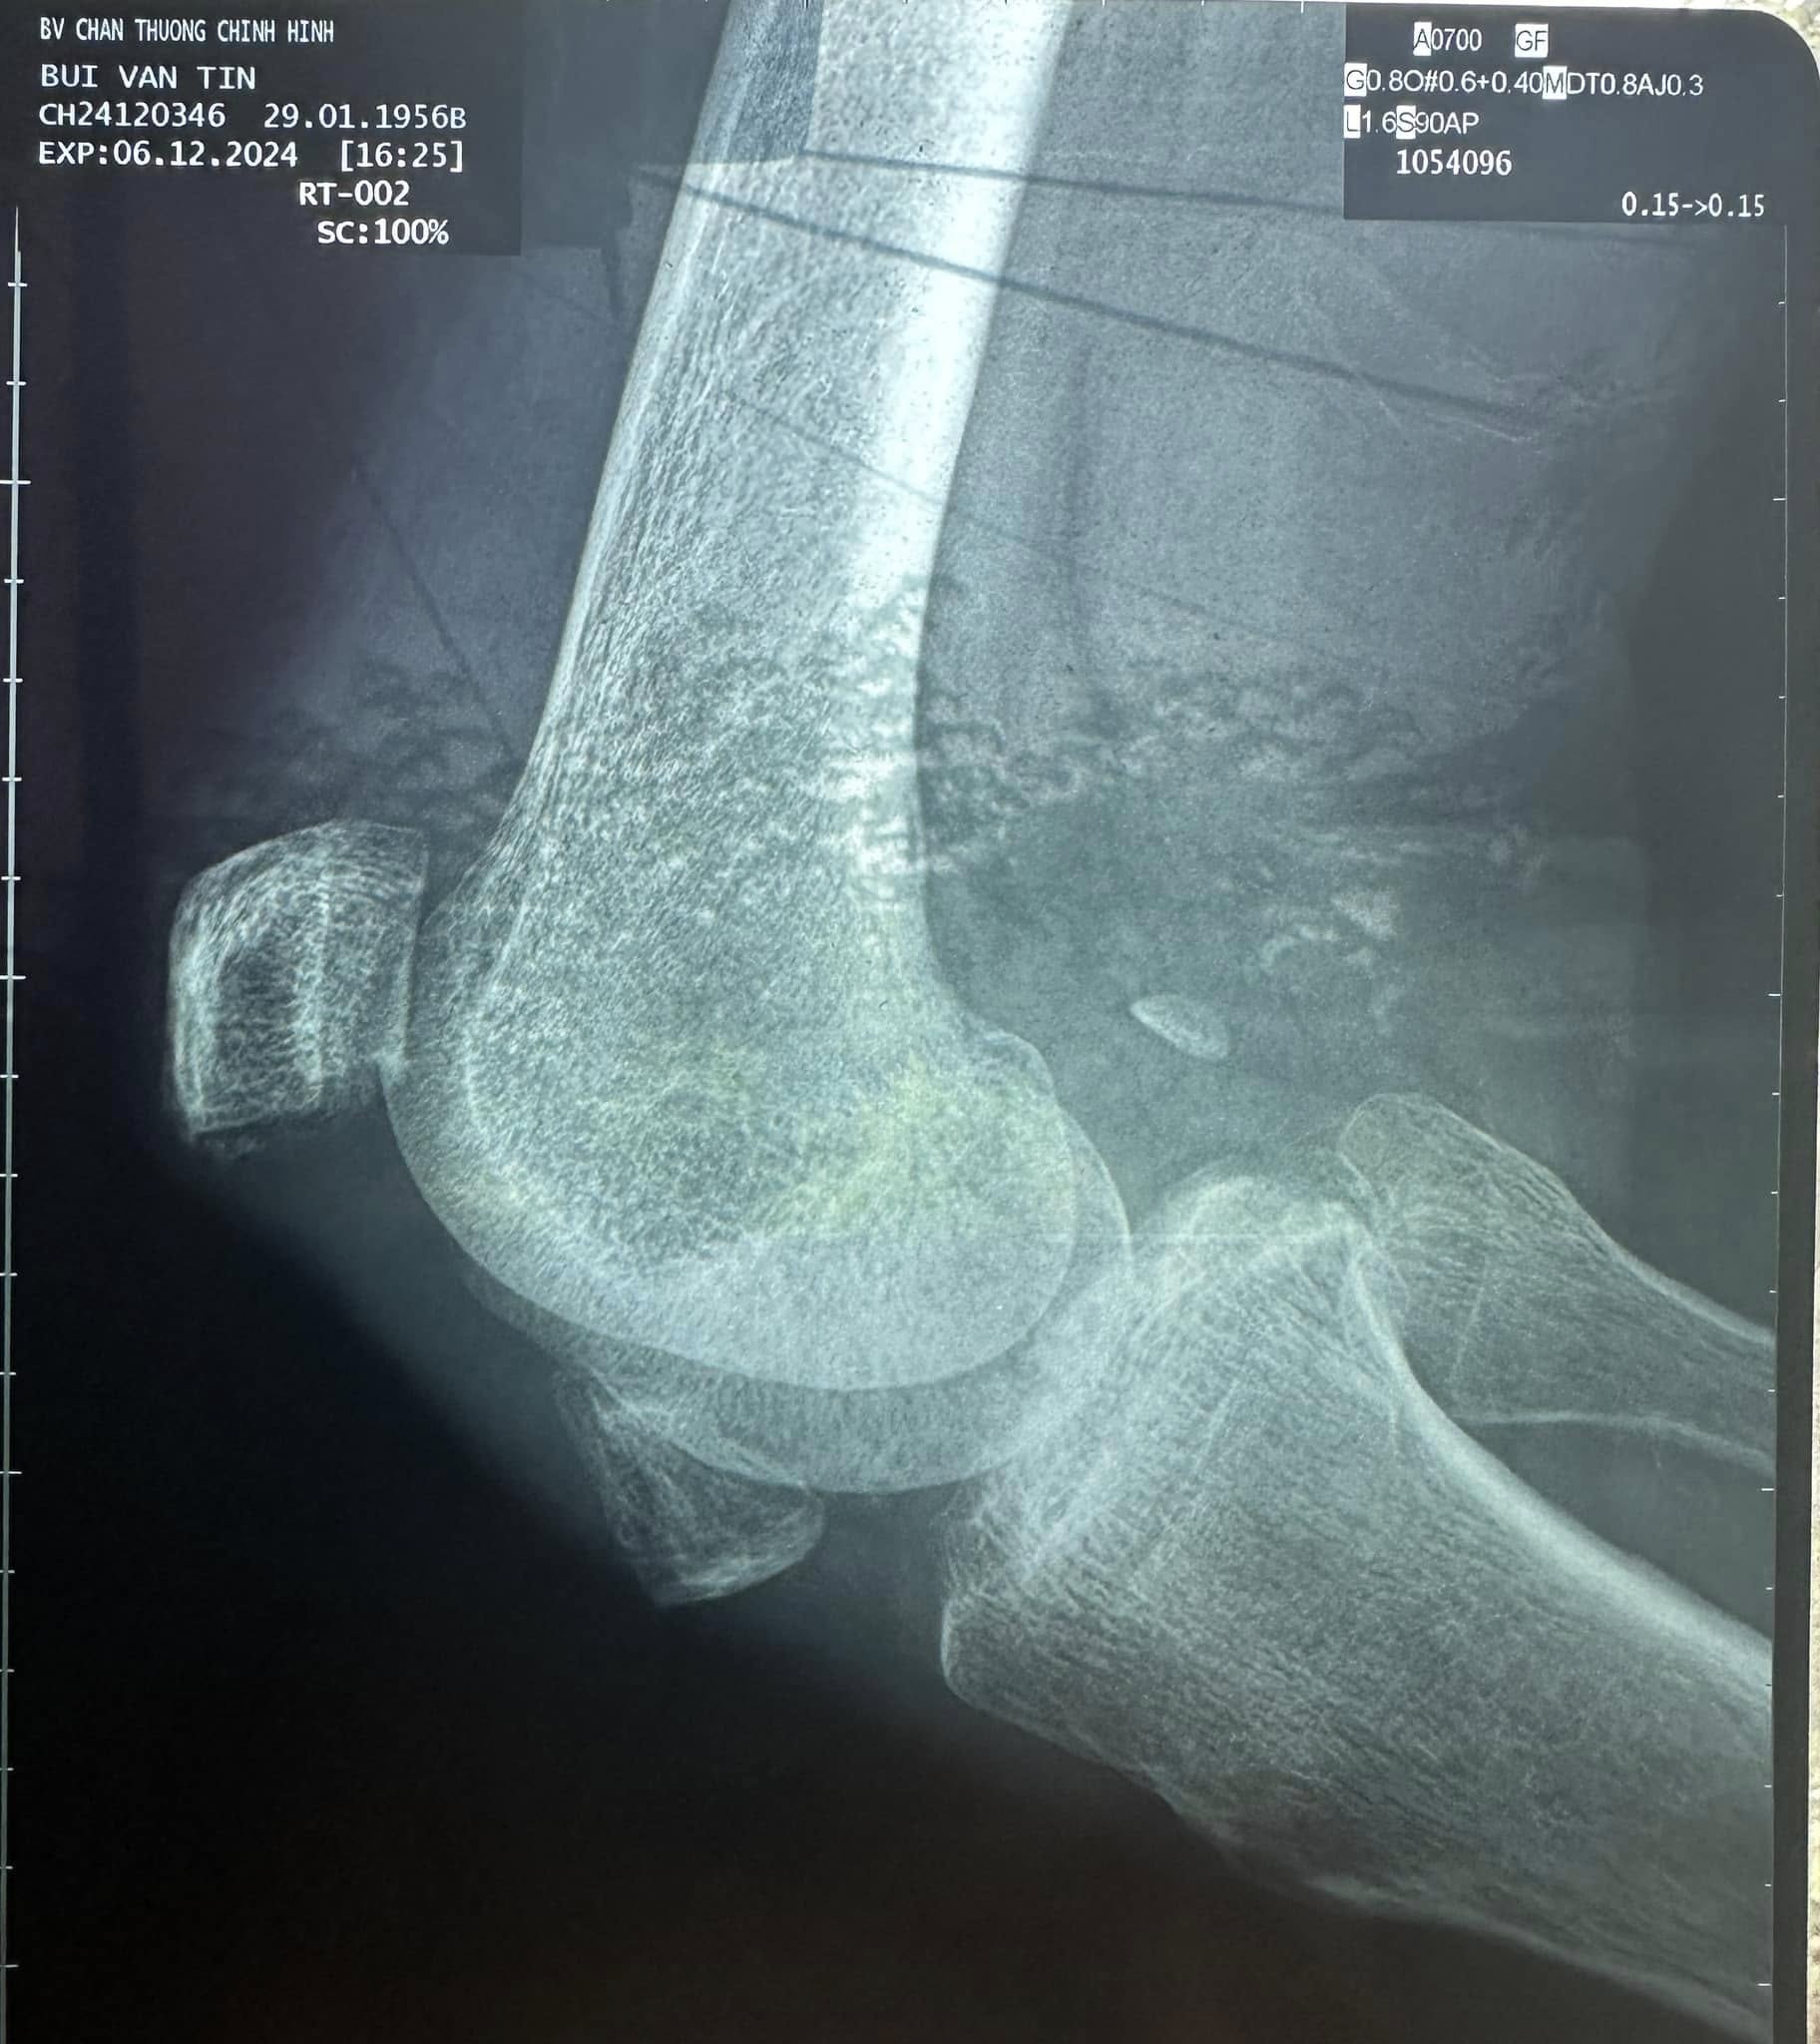

Thương Tín từng là tài tử hào hoa nổi tiếng, được khán giả yêu mến một thời. Tuy nhiên, cuộc sống tuổi xế chiều của diễn viên đình đám lại nhiều bi đát, bệnh tật. Vào tháng 10 vừa qua, NS Thương Tín bị tai nạn và được chẩn đoán gãy xương bánh chè gối khi định gặp gỡ nhạc sĩ Tô Hiếu nhờ tìm kiếm việc làm. Ông bị biến chứng teo cơ, không thể duỗi chân vì không điều trị kịp thời, thậm chí còn có nguy cơ tàn tật vĩnh viễn.

Trên trang cá nhân, nhạc sĩ Tô Hiếu từng chia sẻ về tình trạng cực nguy hiểm của NS Thương Tín: "Chân phải đầu gối bị bể đôi bánh chè khớp gối, bác sĩ nói không thể hồi phục lại được. Chân trái đầu gối bị viêm khớp gối nặng, uống thuốc điều trị lâu dài. Sức khỏe hiện tại rất yếu, khi nào tốt mới mổ".